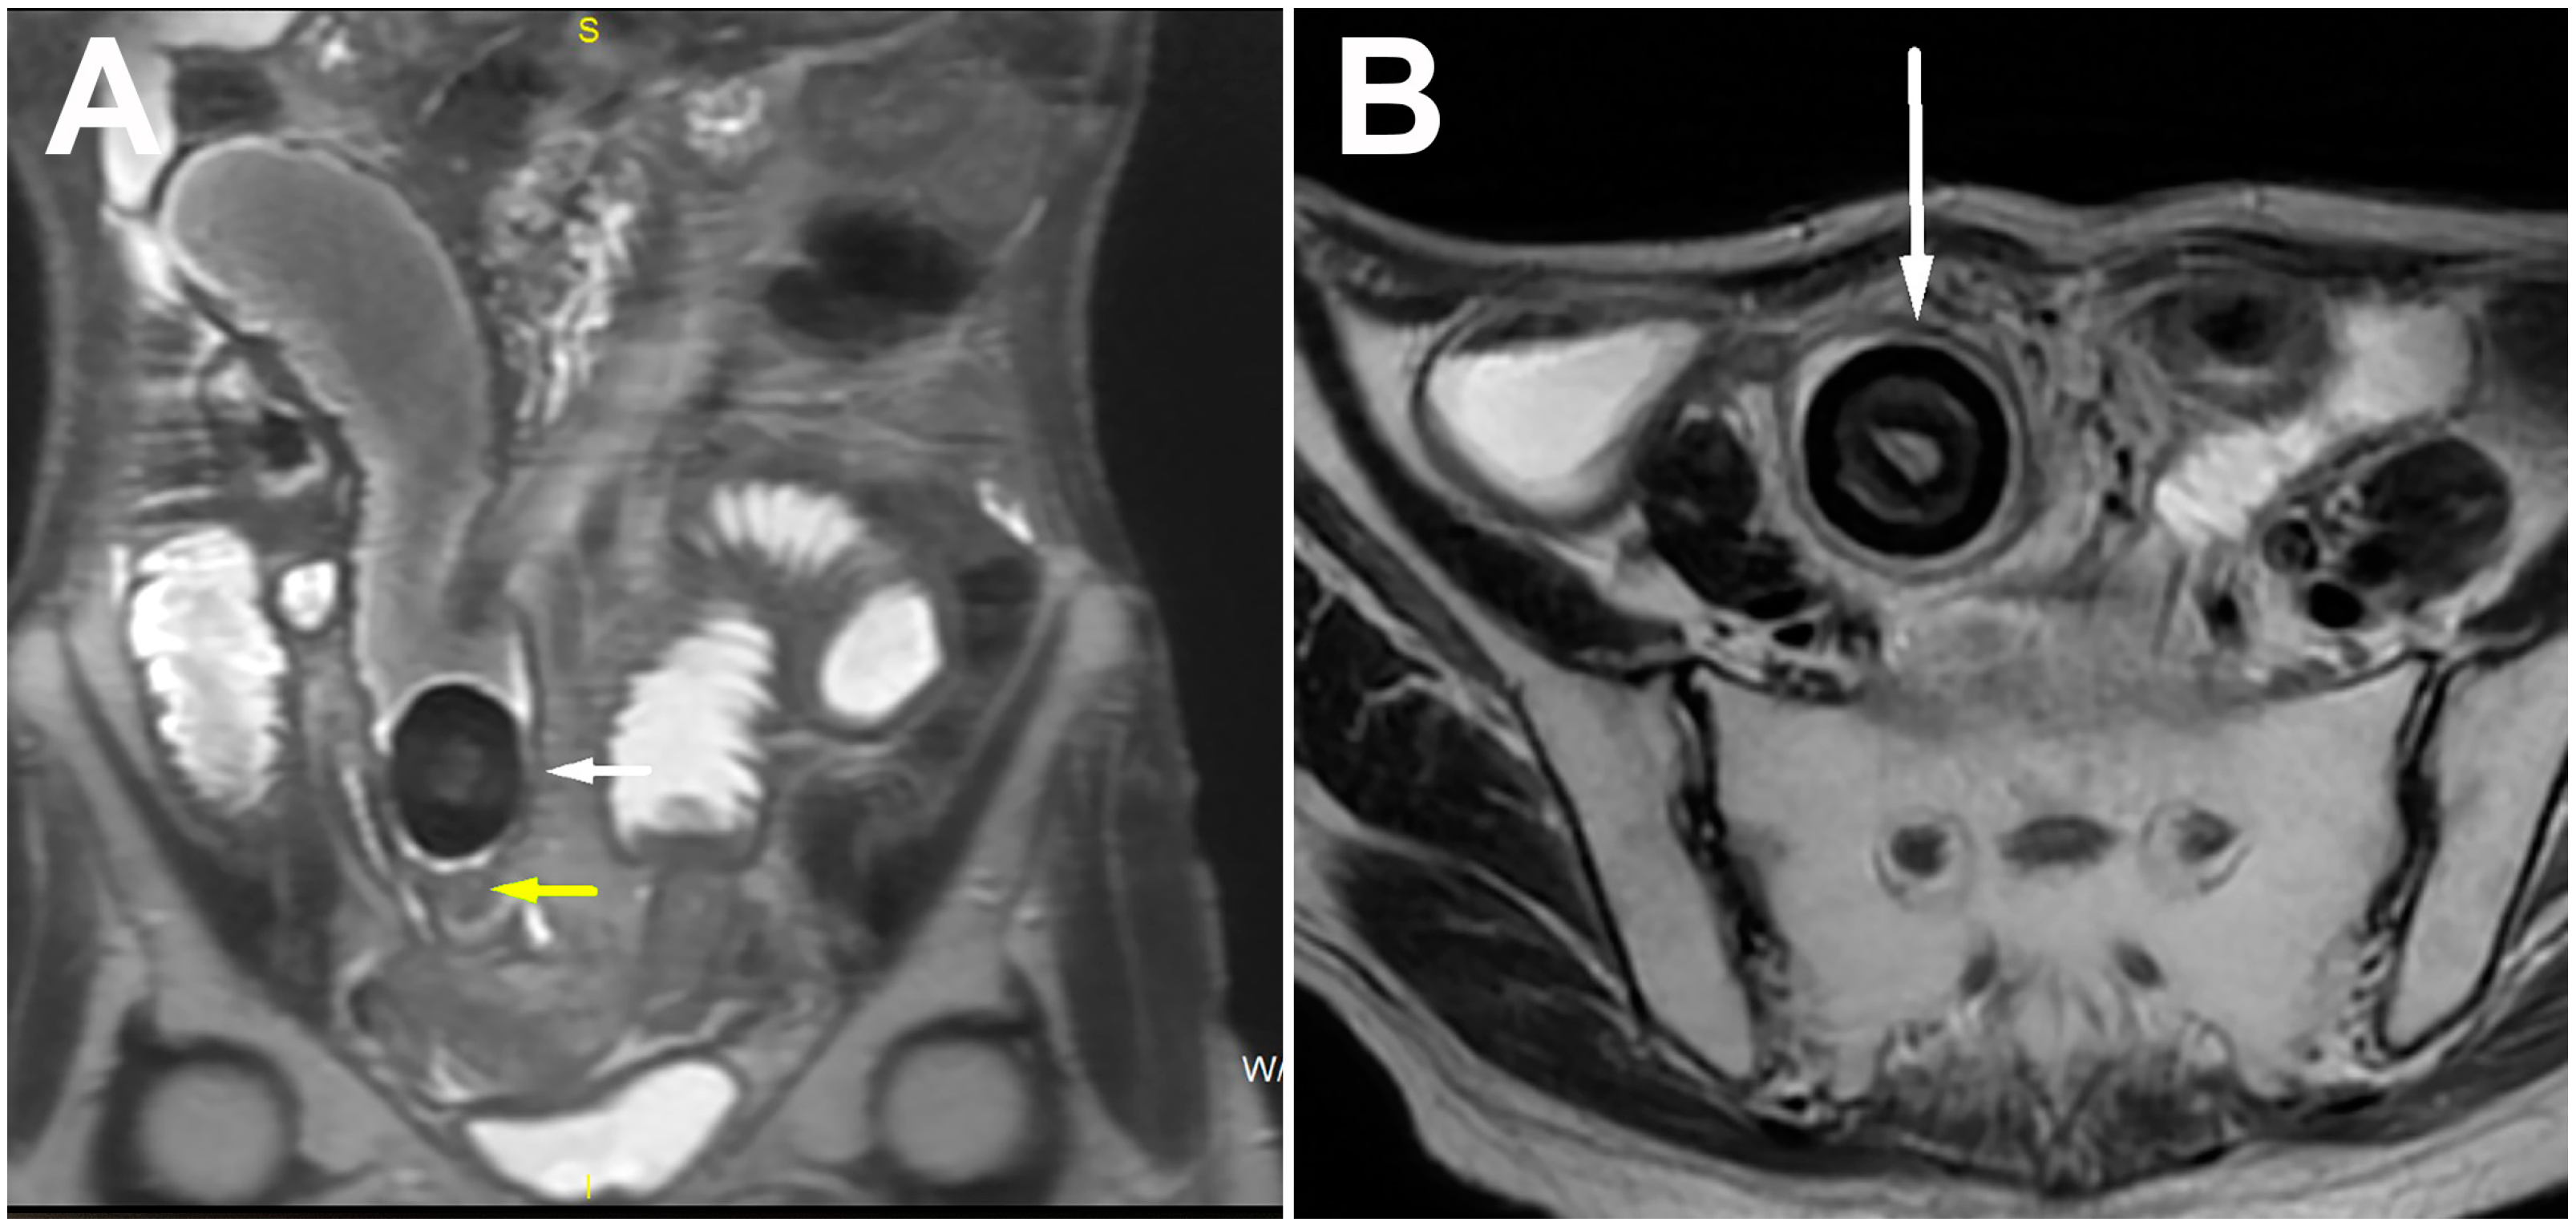

| Calcified bezoar (“Bezoar egg”) | Hyperechoic oval structure with posterior acoustic shadow within the bowel lumen | Oval, clearly demarcated mass with centrally placed gas | T1w and T2w hipointense oval mass with layered structure |

| Non-calcified bezoar (trichobezoar, phytobezoar, lactobezoar) | Arc-like surfaced intraluminal mass with posterior acoustic shadow | Oval or tubular masses with clear boundaries located inside the intestinal lumen, with mottled gas density | Oval mass with low T2w signal and a low to intermediate T1w signal intensity |

| Gallstone ileus | Hyperechoic oval structure with posterior acoustic shadow | Oval calcified or isodense intraluminal mass, presence of pneumobilia and cholecysto-enteric fistula | Oval mass with a homogenously low signal intensity on T1w and T2w |